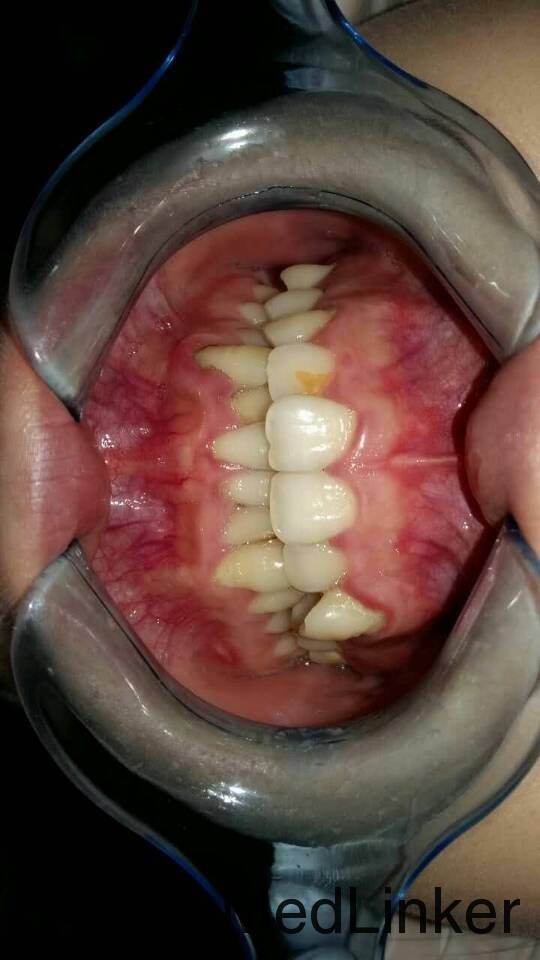

矫正一例

女,15岁,要求矫正